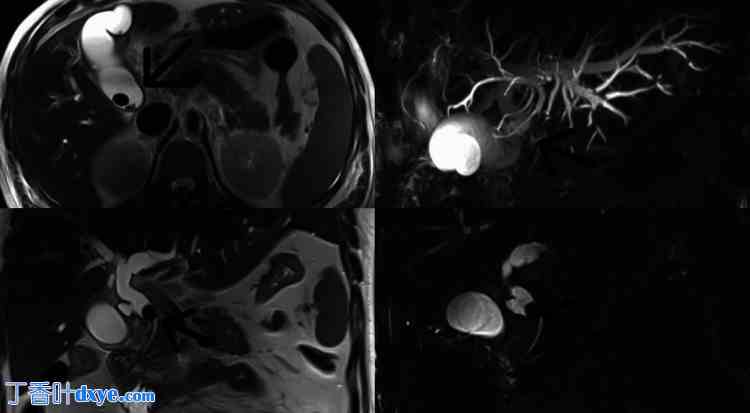

MRCP(图 1)显示 CBD 和肝总管 (CHD) 中存在多个边界清晰的低信号充盈缺损,最大的一个为 14 毫米。近端肝胆管根部、左右肝管、CHD(12 毫米)和 CBD(10 毫米)均扩张。胆囊部分膨胀,胆囊壁水肿、发炎,厚度为 10 毫米,胆囊窝内有轻微脂肪束,提示有胆囊炎。胆囊颈部有约 15 毫米大小的结石,导致胆总管受压,提示有 MS。胆囊颈部和胆总管区域有连续性证据,提示有瘘管形成。

图 1. MRCP 片。

箭头指向显示胆总管 (CBD) 和肝总管 (CHD) 中存在多个边界清晰的低信号充盈缺损。近端肝胆管根部、左右肝管、CHD 和 CBD 均有扩张。胆囊颈部有结石,导致 CBD 受压,提示患有 Mirizzi 综合征。

MRCP:磁共振胰胆管造影